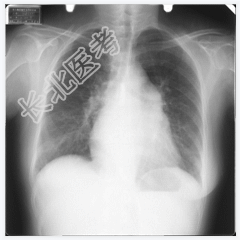

- [材料题] 女,50岁,主诉:胸闷、心悸4个月。听诊:心尖部听到舒张期和收缩期杂音。

- 简答题1、请问该案例诊断是什么?

- 简答题2、请问诊断依据是什么?

- 简答题3、风湿性心脏病临床表现有哪些?